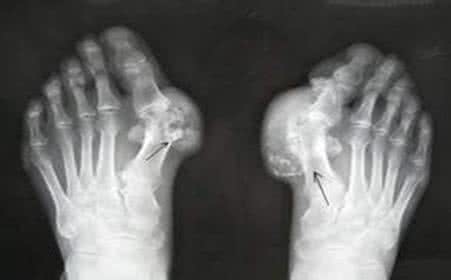

高尿酸血症发展成痛风的过程如下: 血液中的尿酸增加高尿酸血症形成尿酸盐结晶并沉积于体内白细胞吞噬结晶,同时释放出引起炎症的物质关节处发炎, 痛风发作 。 在人体内的…[查看详情]